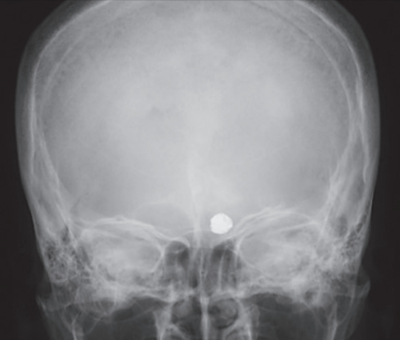

意識レベルは JCSⅠ-2。心拍数 86/分、整。血圧 140/90 mmHg。呼吸数 18/分。SpO₂ 98 %(room air)。後頭部に擦過傷を認める。搬入直後までの記憶がない。心電図に異常を認めない。頭部エックス線写真正面像、側面像及び頭部単純 CTを別に示す。

この患者の 5 年前の既往として考えられるのはどれか。

a. ステント留置術

b. 脳室・腹腔短絡術

c. 穿頭血腫ドレナージ術

d. 脳動脈瘤頸部クリッピング術

e. 脳動脈瘤に対するコイル塞栓術